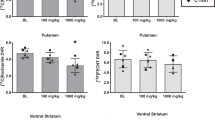

Mean tissue–time activity curves for the basal ganglia (BG) and cerebellum (Cb), the two regions of interest, from the first PET study (n = 5 monkeys) are shown in Figure 1 (top panel, closed symbols). For all monkeys initially anesthetized with 5% isoflurane and maintained on 1.5% isoflurane (Study 1), there was a high uptake of [18F]FCP and a linear rate of washout from the BG, a region with a high density of D2 receptors. Uptake of [18F]FCP in the Cb, a region devoid of D2 receptors, was lower, and the rate of washout was faster than that observed in the BG. When the monkeys were initially anesthetized with 10 mg/kg ketamine (Study 2) before the PET study (Figure 1, top panel, open symbols), there were no apparent differences in tissue–time activity curves compared to the first PET scan.

Tissue-time activity curves (top panel) of [18F]FCP in basal ganglia (circles) and cerebellum (triangles) and the basal ganglia:cerebellum ratios (bottom panel) of [18F]FCP for cynomolgus monkeys initially anesthetized with isoflurane (Study 1; filled symbols) or 10 mg/kg ketamine (Study 2; open symbols). Each point is the mean of data from five monkeys

Normalized peak uptake values (%i.d./cc), postinjection time at which peak uptake occurred and linear half life (t1/2) clearance rates from the BG were determined from the mean tissue–time activity curves. For PET Study 1, the average peak uptake in the BG occurred at about 27.5 min postinjection (Table 1), with a mean normalized peak uptake value of approximately 0.085 (±0.012)%i.d./cc tissue for all test studies. Only monkey 5397 had peak uptake in the striatum later than 27.5 min. In Study 1, [18F]FCP cleared from the BG in a linear manner, with a t1/2 of 140.20 (±6.99) min (Table 1). The between-subject range of washout was 123 to 160 min. When retested with ketamine induction (Study 2), the average peak uptake in the BG occurred at approximately 27.5 min postinjection (Table 1), with a mean normalized uptake value of approximately 0.082 (±0.005)%i.d./cc tissue. In Study 2, the linear rate of washout of [18F]FCP from the BG had a t1/2 of 164.20 (±15.7) min (Table 1), with a between-subjects range of 132 to 215 min. There were no statistically significant differences between Study 1 and Study 2. The time of peak uptake was later in Study 2 as compared to Study 1 in three of the five monkeys, although the %i.d./cc tissue values were not significantly different between the studies (t[4] = 0.10, p > .92). Although there was a trend for higher t1/2 values following ketamine induction (Study 2) as compared to isoflurane induction (Study 1), these differences were not statistically significant (t[4] = 2.51, p > .06).

The mean BG:Cb distribution volume ratio (DVR) of [18F]FCP for Study 1 was 2.48 (±0.12), with a between-subject range of 2.29 to 2.89 ( Table 2). The mean DVR of [18F]FCP for Study 2 was 2.50 (±0.10), with a between-subject range of 2.27 to 2.83 (Table 2). Direct comparisons between Study 1 and Study 2 revealed within-subject variability of DVRs of approximately 2%; these differences were not statistically significant (t[4] = 0.64, p > .55). Graphical representation of BG:Cb time activity curve ratios for the isoflurane- and ketamine-induced anesthesia studies is shown in Figure 1 (bottom panel). As reported previously for this ligand (Mach et al. 1996), the rapid rate of washout of [18F]FCP from the BG and Cb resulted in a high BG:Cb ratio, reaching a peak value of 3.46 (±0.31) at approximately 65 min postinjection in Study 1, when anesthesia was induced by isoflurane. In Study 2, the mean peak BG:Cb ratio was 3.42 (±0.22) at 65 minutes postinjection. There were no statistically significant differences in the BG:Cb ratios (t[4] = 0.23, p > .82) between Study 1 and Study 2. Arterial plasma radioactivity curves and metabolite corrected plasma curves were not significantly different between the first and second PET studies (data not shown) and are similar to data reported previously for this ligand (Mach et al. 1996).